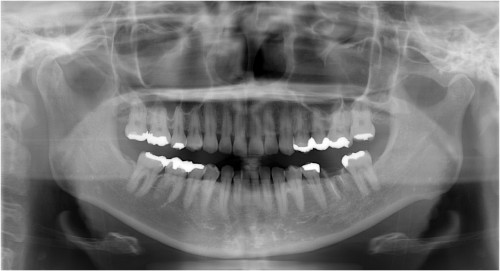

術前

インプラント埋入前